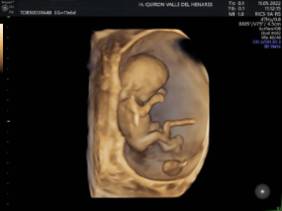

El Hospital Quirónsalud Valle del Henares incorpora un nuevo ecógrafo con tecnología 5 D

El Hospital Quirónsalud Valle del Henares ofrece la posibilidad de realizar ecografías gestacionales 5D. Este tipo de exploración permite obtener una imagen muy realista del bebé y se puede realizar en cualquier etapa de la gestación -aunque lo recomendado es realizarla entre las semanas 28 y 32 de gestación, ya que técnicamente es el mejor momento y es mucho más probable obtener imágenes de buena calidad-.

Al final de la prueba, se entrega a la familia un informe de la ecografía y un soporte digital que contiene las imágenes y los vídeos realizados. Las ecografías 4D y 5D son también llamadas emocionales por la explosión de sensaciones que genera cuando la madre ve por primera vez la imagen del bebé que espera.

"Realizar esta ecografía con nuestro equipo de diagnóstico prenatal tiene un valor añadido -señala la Dra. Rocío Vellido Cotelo, Jefa Asociada de Ginecología y Obstetricia del Hospital Quirónsalud Valle del Henares, dado que quien realiza la prueba es un especialista en la materia, siempre se completa la exploración con un examen morfológico y de perfil biofísico fetal, que permita valorar el estado de bienestar del bebé más allá de la captura de videos y fotografías".